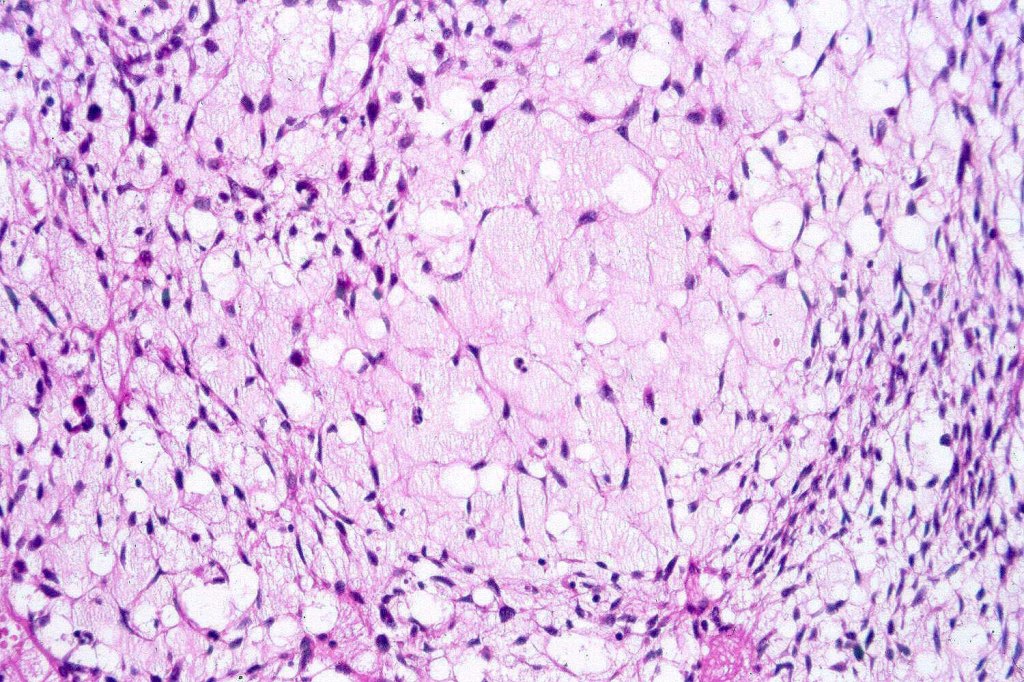

A rare variant of melanoma in which stromal cells produce excess acid mucopolysaccharides inprting a striking myxoid quality. The mucin is Alcian blue & colloidal iron positive, DPAS negative and the melanoma cells stain with typical markeres including S100 & HMB45. It may be seen in primary, recurrent or most often in metastatic lesions. The tumor cells are typically small although occcasionally they are epithelioid. Melanin is often sparse or even avsent making diagnosis difficult. In some examples, a pseudoglandular appearance is seen.

The differential diagnosis is very wide and can include numerous myxoid soft tissue tumors and epthelial mucin-secreting carcinomas. Diagnosis depends on clinical history, mucin stains and the judicious use of immunohistochemistry.